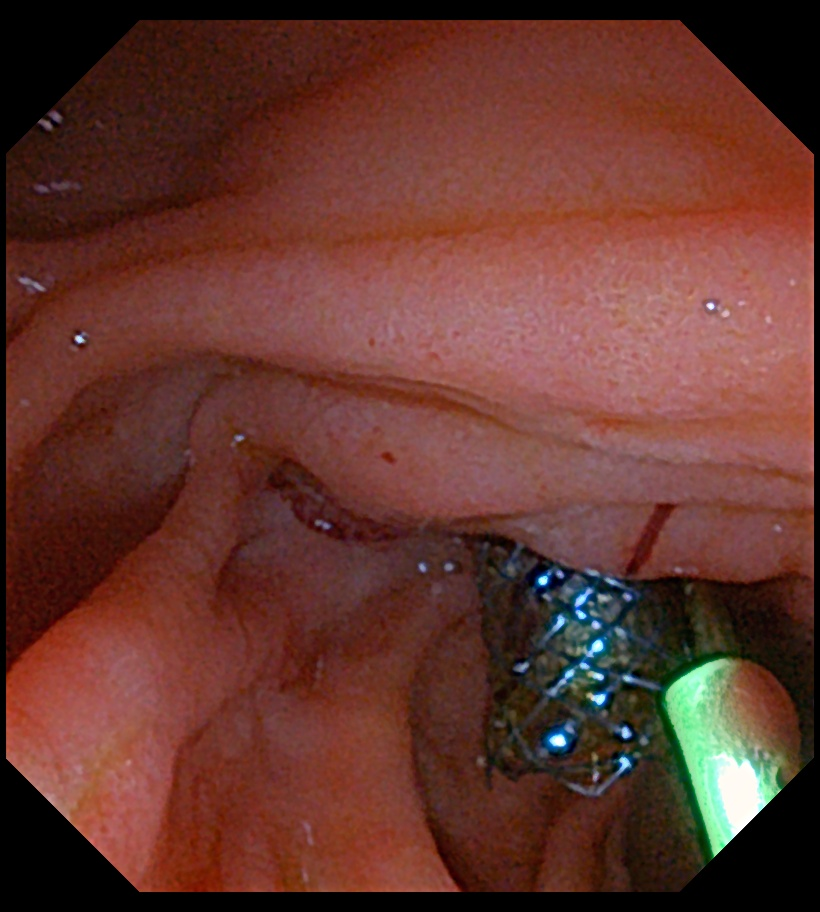

随后,植中敬沿胆总管导丝顺利放置全覆膜金属支架一枚,支架顺利释放并扩张,胆汁引流顺畅,再沿导丝顺利放置一胰管支架以维持胰液引流通畅。

沿导丝成功放置胆管全覆膜支架及胰腺塑料支架

内镜下可见胆管金属支架及胰管支架